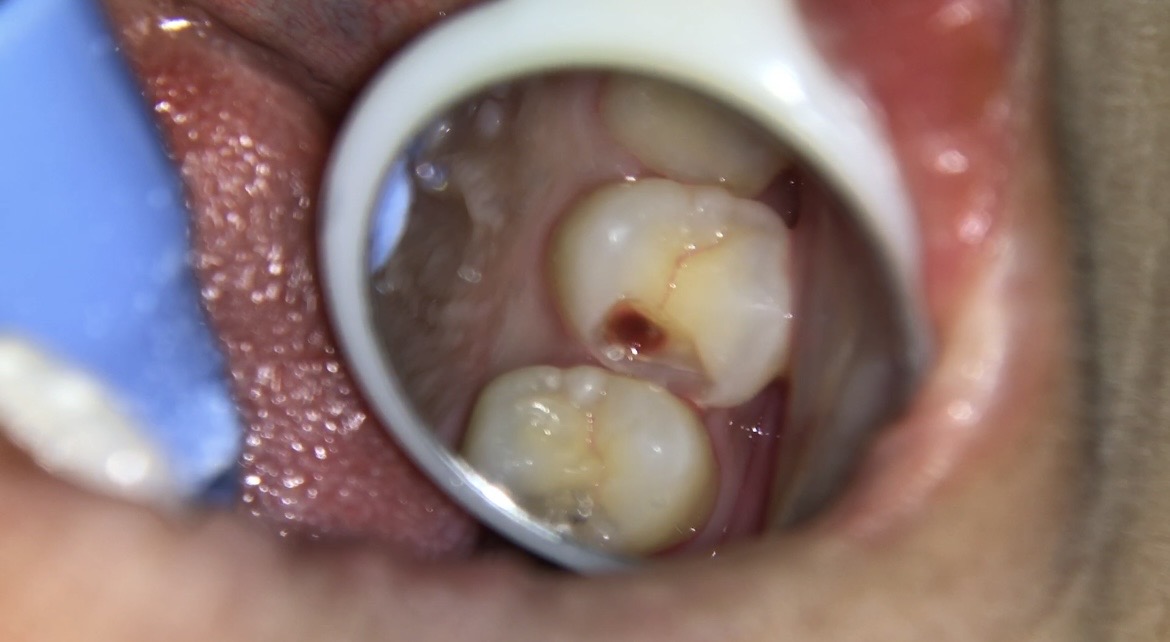

【処置前】削る前→虫歯除去

削ると歯と歯の間から虫歯が進行し、まだ虫歯が残ってる状態になります。

MTAセメント詰めた後↓ ↓ ↓